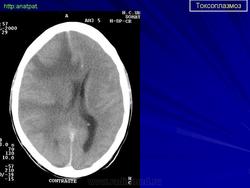

Пато морфологи я. Патоморфологические изменения при приобретенном токсоплазмозе изучены в экспериментах на животных. Установлено, что в центральной нервной системе развиваются явления некротического перивентрикулита, мелкие очаги некроза в субкортикальном белом веществе. В сосудах головного мозга, мягкой мозговой оболочки и хориоидальных сплетениях отмечаются признаки серозно-пролиферативного воспаления. Обнаруживаются также глазные патологоанатомические изменения (типа ретинита, хориоидита, иридоциклита) и изменения во внутренних органах (сердце, легкие, печень, селезенка).

Врожденный токсоплазмоз чаще, чем приобретенный, приводит к летальному исходу. В головном мозге умерших обнаруживаются более или менее значительные очаги обызвествления, участки размягчения мозгового вещества, полости, заполненные жидкостью. Как правило, отмечается гидроцефалия, обусловленная воспалительной и рубцовой облитерацией водопровода среднего мозга, отверстий Люшка или других участков ликворных путей. Истон-чение вещества полушарий мозга может достигать степени их полного исчезновения.

Особенно характерна триада симптомов: хореоретинит, гидроцефалия, очаги обызвествления в головном мозге. Кроме того, отмечаются менингеальные знаки, тонические и клонические судороги, парезы, параличи, олигофрения.

Неврологические симптомы могут сочетаться с пневмонией, миокардитом, гепатоспленомегалией, с выраженной желтухой. В спинномозговой жидкости отмечается лимфоцитарный плеоцитоз (до 500 • 106 в 1 л), ксантохромия (“канареечный” ликвор). На рентгенограмме черепа обнаруживаются обызвествления в глубинных отделах головного мозга, сосудистых сплетениях. Как и приобретенный, врожденный токсоплазмоз может протекать остро, подостро и хронически.

Церебральный токсоплазмоз.

Церебральный токсоплазмоз